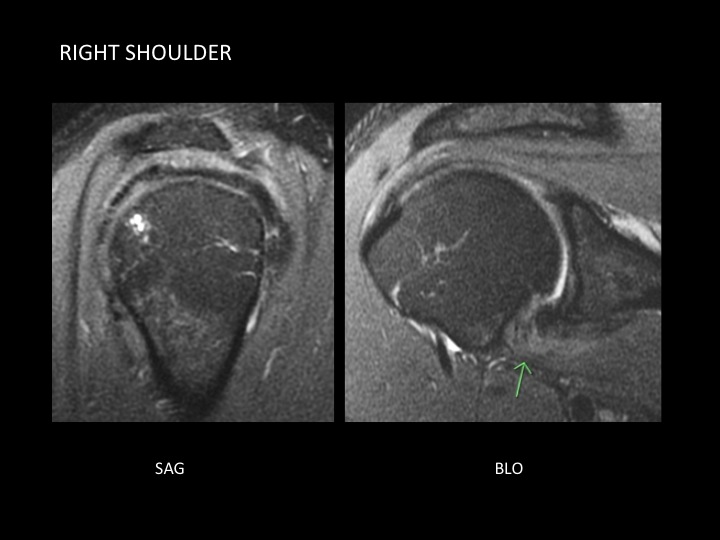

45 yr old male with 6 months bilateral shoulder pain and LROM

Figure 2 for case adhesive capsultis

Figure 2

Despite the female predilection for adhesive capsulitis, here is a case of bilateral adhesive capsulitis in a male, more severe on the left. Up to 40-50% sequential bilateral involvement has been reported, though simultaneous bilaterality is rare. In the left shoulder, bright signal at the articular surface of the cuff near the supraspinatus insertion is more likely capsular inflammation than cuff pathology (not seen on the Rt where involvement is more limited to the axillary recess). Note the disproportionate fluid distention of the biceps sheath, more apparent on the left.

adhesive capsultis